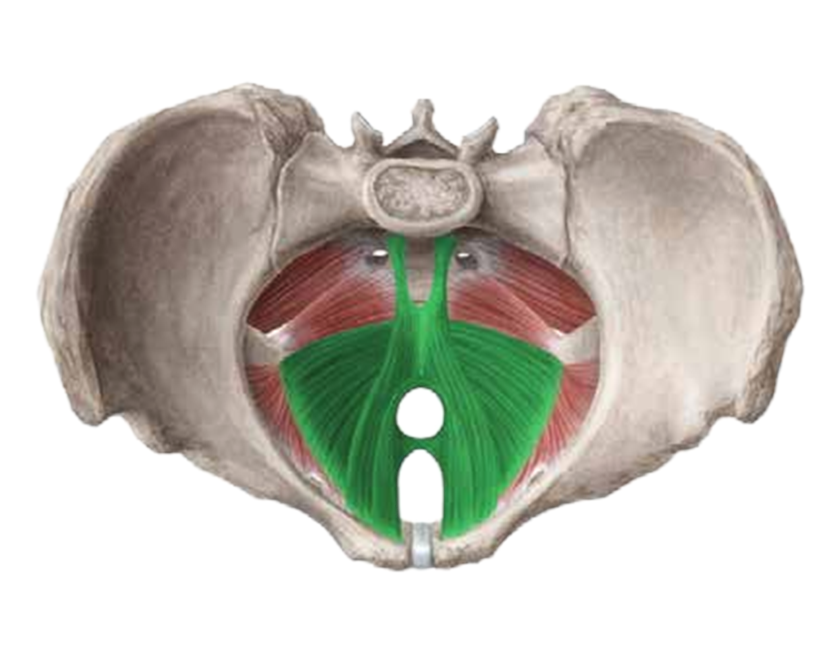

Ein funktionaler Beckenboden hat eine zentrale Rolle für die Stabilität der unteren Lendenwirbelsäule und verhilft zu einer besseren Körperhaltung. Zu schwache oder verkrampfte Gesäßmuskeln können Schmerzen verursachen, da durch diese viele Nerven (u.a. der Ischiasnerv) durchziehen und komprimiert werden können.

Der Beckenboden als Teil der (Rumpf)Stabilität hat einen wesentlichen Einfluss auf die Leistungsfähigkeit und Effizienz des gesamten Bewegungs- und Halteapparats. Das Verletzungsrisiko wird gesenkt

Mittels modernster Magnetfeldtechnologie aktiviert, stimuliert und kräftigt der PelviPower-Stuhl die Strukturen des Beckenbodens. Um eine Stärkung bis in die tiefsten Muskelschichten zu erzielen, lösen die Magnetfeldimpulse bis zu 25000 Kontraktionen aus und trainieren so gezielt Ihren Beckenboden. Die Eindringtiefe beträgt je nach gewählter Intensität 5 bis ca. 15 cm. Der Wirkfelddurchmesser beträgt bis zu 40 cm.

Der Beckenboden ist das Kraftzentrum des Körpers - die Basis - ein wesentlicher Teil der Körpermitte. Ein trainierter, starker Beckenboden hilft dabei, vielen Beschwerden wie Blasenschwäche und Inkontinenz vorzubeugen und/oder in den Griff zu bekommen. Darüber hinaus wird die Libido und sexuelle Empfindungsfähigkeit gestärkt. Rückenbeschwerden werden gemindert, die körperliche Spannkraft, Haltung, allgemeine Fitness und Vitalität verbessert.